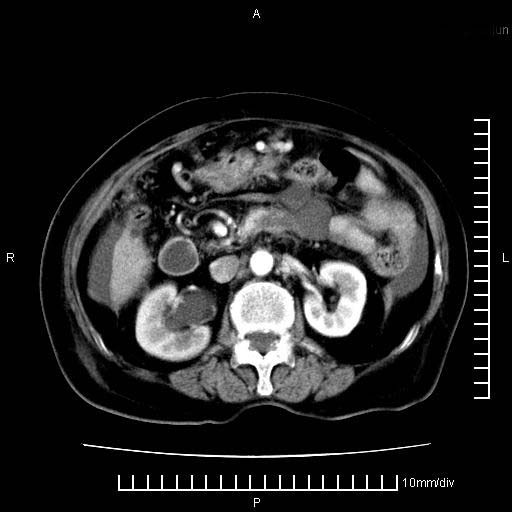

标题: CT28280:腹部增强:女性,80岁

上腹疼痛月余,外院核磁诊断胰腺癌。现临床示右下腹可明显触及包块,可片子上怎么没有看到?

1.胰腺颈体部癌。

2。腹腔积液。

3。右胸腔积液,伴右肺下叶部分萎陷。

4。右肾盂囊肿。

胰腺体部癌累及周围器官,腹膜、粘连

1。胰腺ca伴腹膜腔转移

2。肝左叶低密度灶,考虑转移可能

胰腺体部癌累及周围器官,腹膜、粘连,临床摸到的可能是粘的组织

胰腺结构模糊,胰尾部见囊性包块,周围脂肪密度增高,左肾前筋膜增厚,胸水、腹水。不符合胰腺ca伴腹膜腔转移。考虑胰腺炎伴假性囊肿形成、胸腹腔积液。

右肾盂囊肿。

1)考虑胰腺癌并胰腺假性囊肿形成。2)肝内低密度灶,不排除转移。3)右肾盂积水。4)腹水。5)右侧胸腔积液并右肺下叶部分膨胀不全。